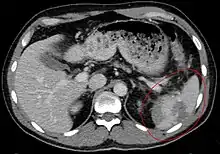

Traumatic rupture of the spleen on contrast enhanced axial CT (portal venous phase)